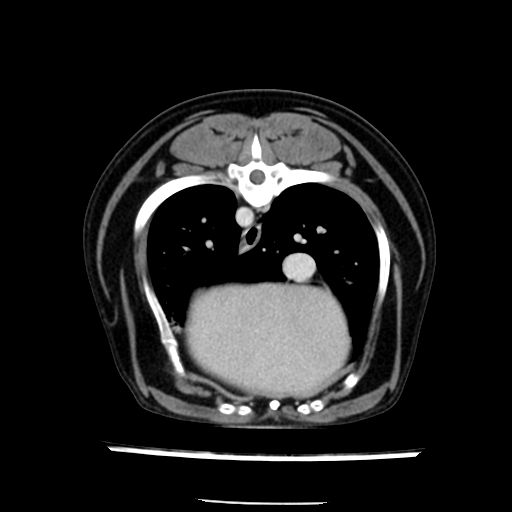

prescritto esame TAC

sequenza immagini limitata al fegato reni e surreni

le immagini ecografiche rispetto alla tac datano circa 7 mesi prima ,le surrenali sono normali nonostante il test acth sia risultato positivo .all’esame TAC dopo diversi mesi risultano aumentate armonicamente nel volume e si individua un forte sospetto di adenoma ipofisario .

sospetto adenoma ipofisario vs. meno probabilmente meningioma della base; intertiziopatia polmonare; lesione espansiva epatica, verosimilmente del lobo laterale sinistro, di sospetta natura neoplastica; lesioni spleniche di natura da definire; iperplasia/ipertrofia delle ghiandole surrenali, bilateralmente; vertebra di transizione del rachide toracico; tenosinovite cronica del muscolo bicipite brachiale di destra.

- l’esame tac e’ stato eseguito circa quattro mesi dopo la prima ecografia che non aveva messo in evidenza aumento del volume surrenalico (vedi immagini) ma solo la lesione epatica, la presenza di PU PD aveva portato ad un controllo per l’ ipercorticosurrenalismo confermato dal test act , in questo caso, si deduce che i sintomi di ipercorticosurrenalismo legati all’adenoma sono comparsi prima delle modificazioni surrenaliche, quindi in caso di sospetto ,a mio avviso e’ buona norma eseguire prima il test di stimolazione e dopo L’ECOGRAFIA per tentare una classificazione eziopatogenetica . La Tac si e’ quindi dimostrata molto valida in sensibilita’ e specificita’ riguardo la patologia surrenalica in quanto in grado di vedere o fortemente sospettare (ovviamente meno sensibile della RM) un piccolo adenoma ipofisario e le alterazioni morfovolumetriche della surrenale.

la tac dopo 7 mesi permette misure tridimensionali 5,2 x 9,2 x 4,5 cm (forma piu’ allungata )